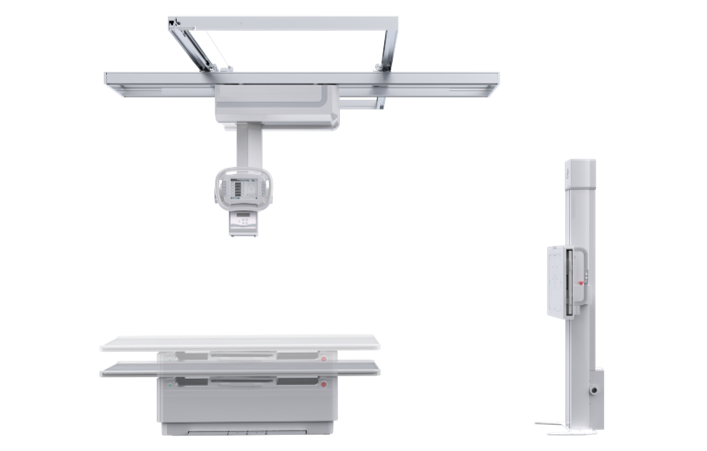

PLD7600

多功能悬吊动态DR

一机多用 PLD7600

集静态DR摄影与动态的透视、造影功能于一身,可进行头部、胸部、腹部和四肢等部位的DR静态摄影、各种动态及造影检查,还能在可视的情况下完成高清DR点片,有效避免传统静态DR盲拍造成的漏诊和误诊,满足多种临床诊断需求。

搭载17x17英寸动态平板探测器,动态帧率高达30帧/秒,突破传统盲拍局限,通过动态实时连续成像,对于重叠部位、易被遮挡的病灶进行多角度动态观察,瞬时实现高清点片,提升筛查诊断的精准性。